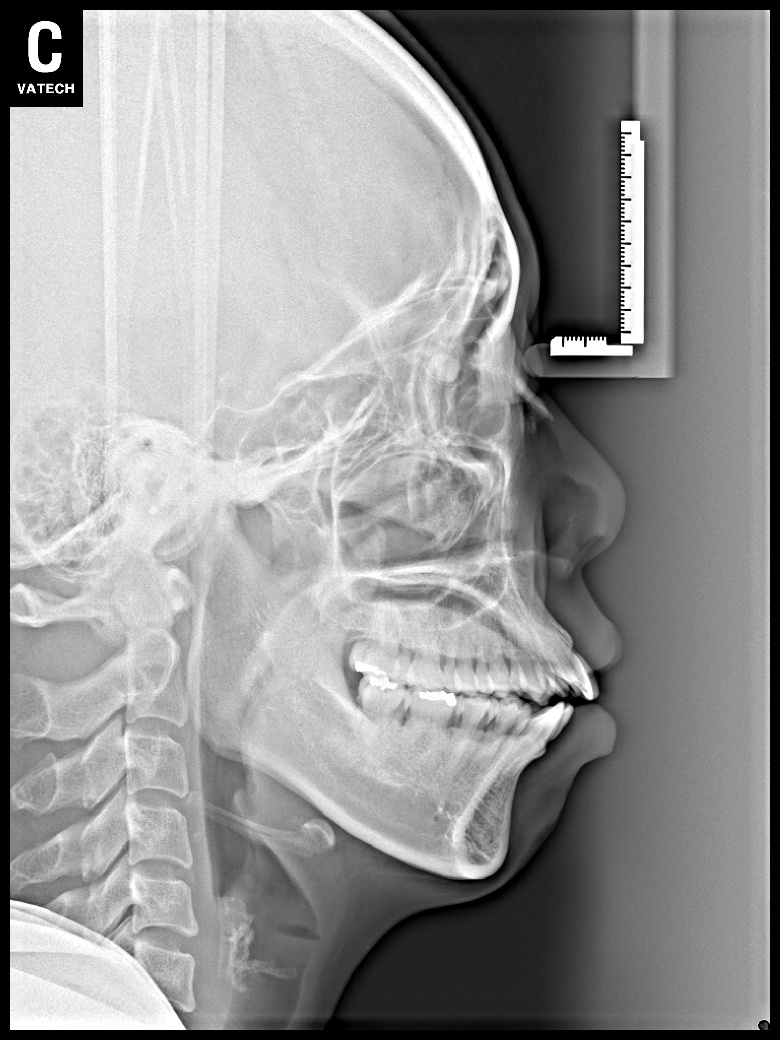

치료 전 사진입니다.